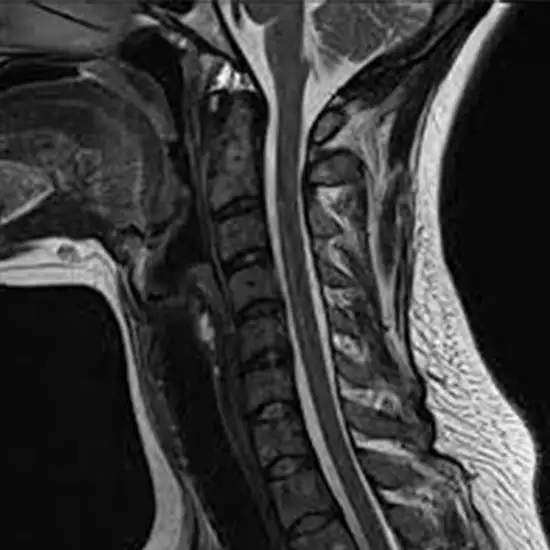

MRI of the neck images the internal structures of the neck. This test can evaluate symptoms such as neck pain, arm or leg weakness, and neck lumps. An MRI of the neck can reveal aneurysms, tumors, infections, and other neck-related problems.